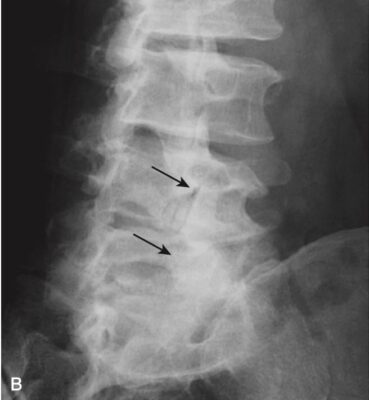

- Với tuổi tác ngày càng cao, nhân nhầy dạng gel bình thường trở nên mất nước và thoái hóa. Quá trình này dẫn đến giảm dần chiều cao của khoang đĩa đệm. Đôi khi, sự khô hoá đĩa dẫn đến giải phóng khí nitơ từ các mô xung quanh đĩa đệm, tạo nên hình ảnh đậm độ khí trong khoang đĩa đệm, gọi là hiện tượng đĩa chân không (vacuum disk phenomenon). Đĩa chân không là một dấu hiệu biểu hiện thoái hoá đĩa đệm giai đoạn muộn (Hình 7).

- Bệnh thoái hóa đĩa đệm trên phim X quang thường quy

- Có sự thu hẹp khoang đĩa đệm (hẹp khe “khớp”). Bản thân các thân đốt sống cũng có những thay đổi.

- Các mặt thân đốt (bản tận) của các thân đốt sống tiếp giáp với nhau bị xơ cứng (đặc xương). Có các gai xương nhỏ ở rìa của các thân đốt sống tại mỗi khoang đĩa đệm (xem Hình 7).

- Đồng thời, thường có sự thoái hóa của vòng xơ bên ngoài, tạo nên các gai xương lớn hơn ở các bản tận so với các gai xương do thoái hoá nhân đệm.

- Cần lưu ý rằng các gai xương là một dấu hiệu rất thường gặp, tỷ lệ tăng khi tuổi càng tăng, và phần lớn những người có gai xương ở cột sống là không có triệu chứng.